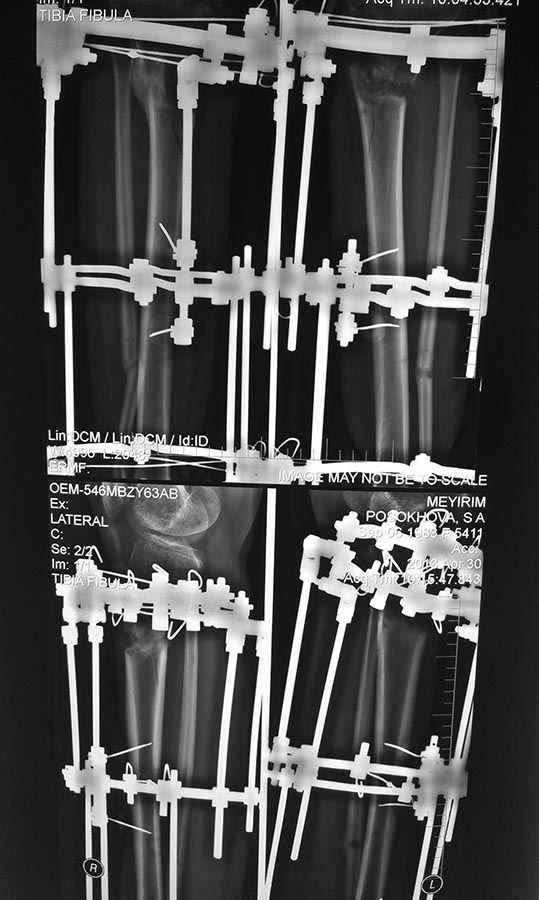

Нет сращения после корригирующей остеотомии, АВФ

Увадаемые коллеги! Нужна Ваша помощь. Пациентка 1983 г/р оперирована в Кургане: двухсторонняя корригирующая остеотомия в/3 обеих голеней, АВФ.

Прошло уже чуть более 6 мес (ко мне попала месяц назад). В последний месяц, видя недостаточность костной мозоли принимала пролиа, альфа д3, кальций. Но за истекщий месяц мозоль не изменилась ни на грамм. Мои соображения: заменить АВФ на БИОС. Поделитесь вашими пожалуйста.

Неплохо бы иллюстрировать вопрос снимками с захватом коленного сустава, чтобы на прямой проекции было видно целиком центральный отломок. А тут для левой конечности еще и профиль перекрыт железом.

Диагноза нет, коррекция косметическая. Назначаем, т.к. есть протоколы диагностики и лечения, утвержденные минздравом, в которых эти глупости прописаны, и есть комитет контрола качества оказания медицинских услуг, который проверяет качество лечения по протоколам. Там где перекрыто металлом справа, есть сращение б/б кости но только 50% ширины диафиза по латеральной поверхности, боюсь тут тоже просто снять нельзя АВФ, произойдет варуная деформация. Спасибо за отклик.

Судя по остеосинтезу, с трудом верится, что это сделано в РНЦ "ВТО". Промежуточная опора расположена на огромном отдалении от остеотомии, в ней одна сквозная спица и две консоли. Стабильность оставляет желать лучшего. Это не похоже на применяемые в нашем центре методики.

Уважаемые коллеги, а можно может быть идиотский вопрос? Рентгенограмма нижняя левая - положение суставной поверхности большеберцовой кости по отношению к оси большеберцовой кости. Для чего создано такое антекурвационное положение?

Это положение отломков при дистракции возникает из-за тяги икроножных мышц и говорит о качестве фиксации прокимального отломка или скорости дистракции. При неадекватности первого или второго возникает антекурвация.